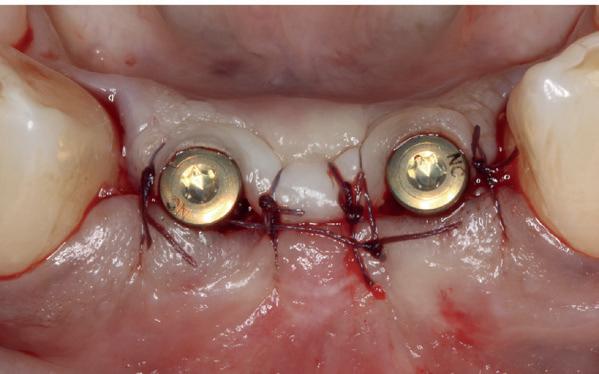

pincisies met hechtingen naar het buccale en coronale deel getrokken en aldaar ingehecht. Met twee incisies werd ook de emergence profile gecreëerd (afbeelding 6-13). Voor een goede genezing van het

5. Beginsituatie voor behandeling

6. VISTA techniek twee hulp incisies

7. Vervaardiging tunnel met tunnelinstrumenten

8. Geoogst bindweefseltransplantaat uit palatum

9. Na de-epithelialiseren van transplantaat

10. Inhechten van een collageenspons in het donorgebied

11. Middels hechtingen het op de juiste plek trekken van het transplantaat

12. Transplantaat ingehecht

13. Occlusaal beeld verdikking van de zachte weefsels

14. Direct postoperatief plaatsen

van de essix met 2 dummy tanden

15. Twee weken post operatief

16. Creëren van een duidelijke indeuking in de mucosa voor emergence profile

17. Genezing van het palatum

18. Etsbrug frontbeeld

19. Etsbrug palatinaal